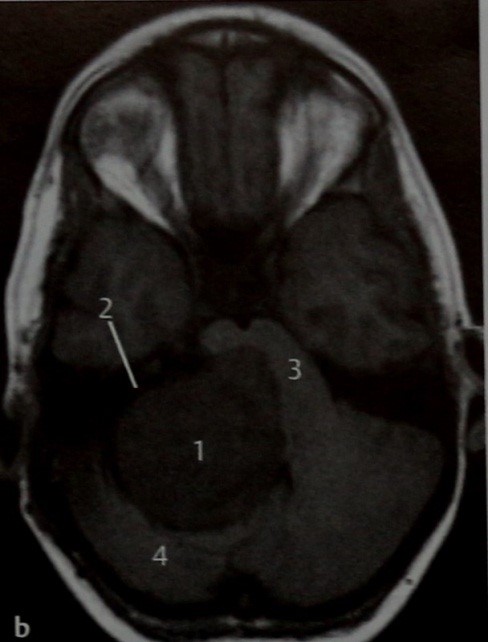

МРТ: Т1- (b) и Т2-взвешенное (с) изображения и Т1-взвешенное изображение с контрастным усилением (d) в горизонтальной проекции. Гигантская опухоль, локализующаяся в области мостомозжечкового угла (Т); отмечаются гипоинтенсивный сигнал на Т1 -взвешенном изображении и гиперинтенсивный - на Т2-взвешенном изображении и усиление сигнала после введения КС. Контрастного усиления внутреннего слухового прохода (2) не происходит. Хотя такая картина для шванномы менее типична, исключить эту опухоль нельзя, учитывая ее округлую форму и ряд других особенностей. Отмечается выраженная компрессия ствола мозга (3) и мозжечка (4). Контрастное усиление содержимого сигмовидного синуса (5) в сочетании с гиперинтенсивным сигналом на Т1 -взвешенном изображении указывает на тромбоз синуса.